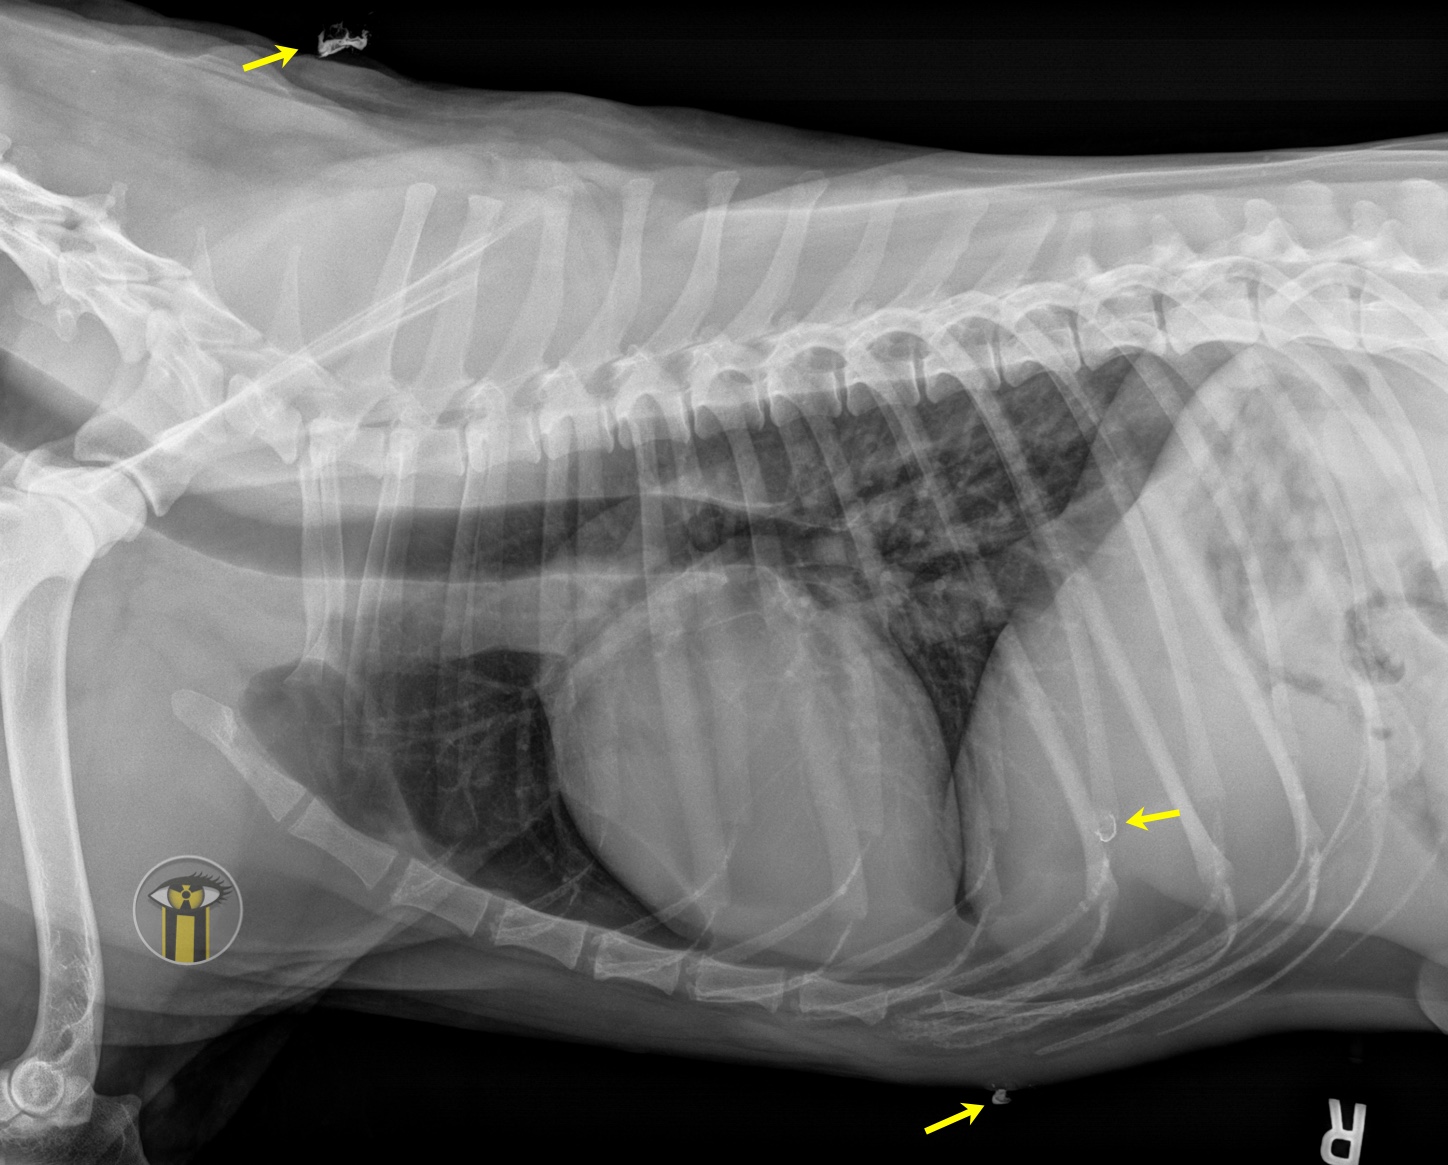

Latérale droite baryum